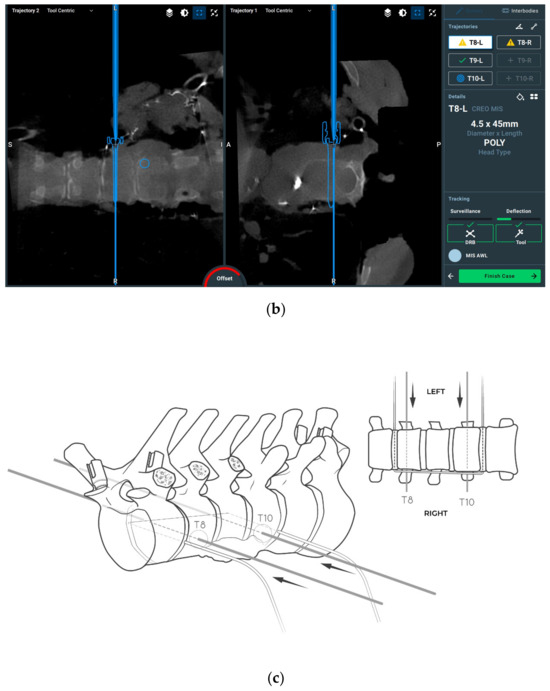

2.3. Surgical Planning

2.4. Surgical Procedure